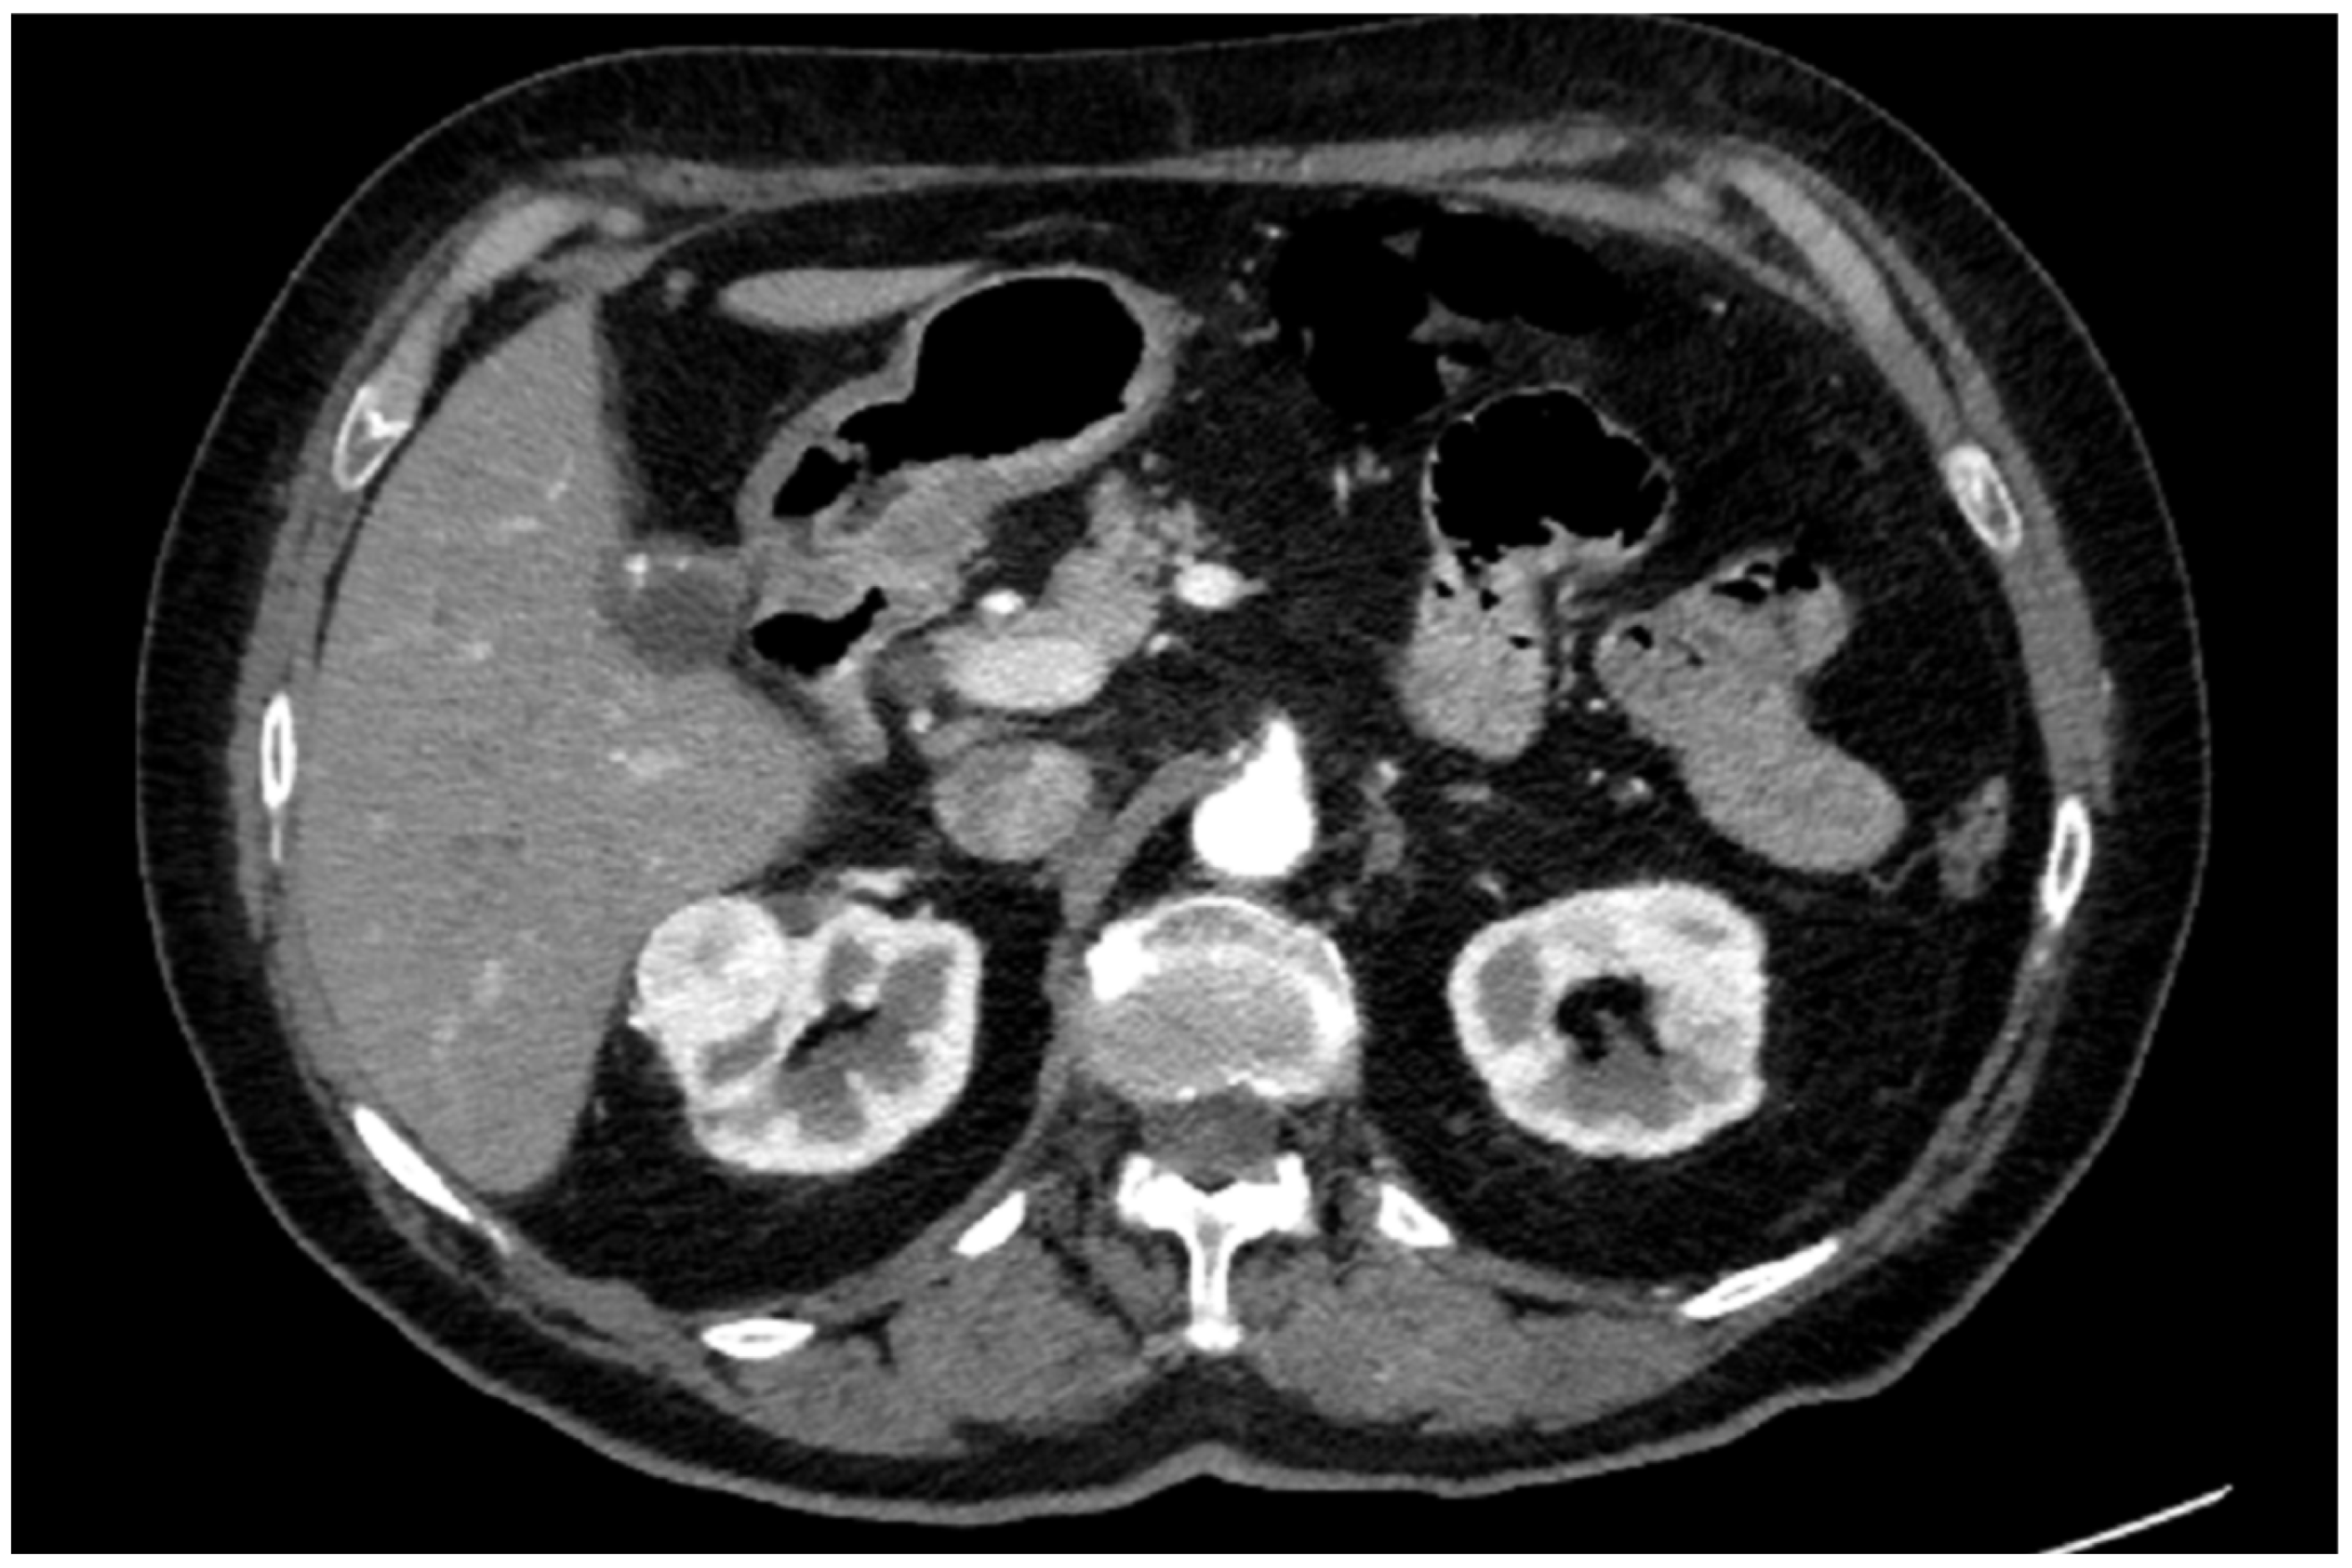

A preoperative contrast-enhanced abdominal CT scan (1.5 mm thickness) confirmed a 35 × 25 mm renal lesion located on the anterior surface of the upper pole of the right kidney (Figure 1).

Figure 1. Axial slice of CT scan.